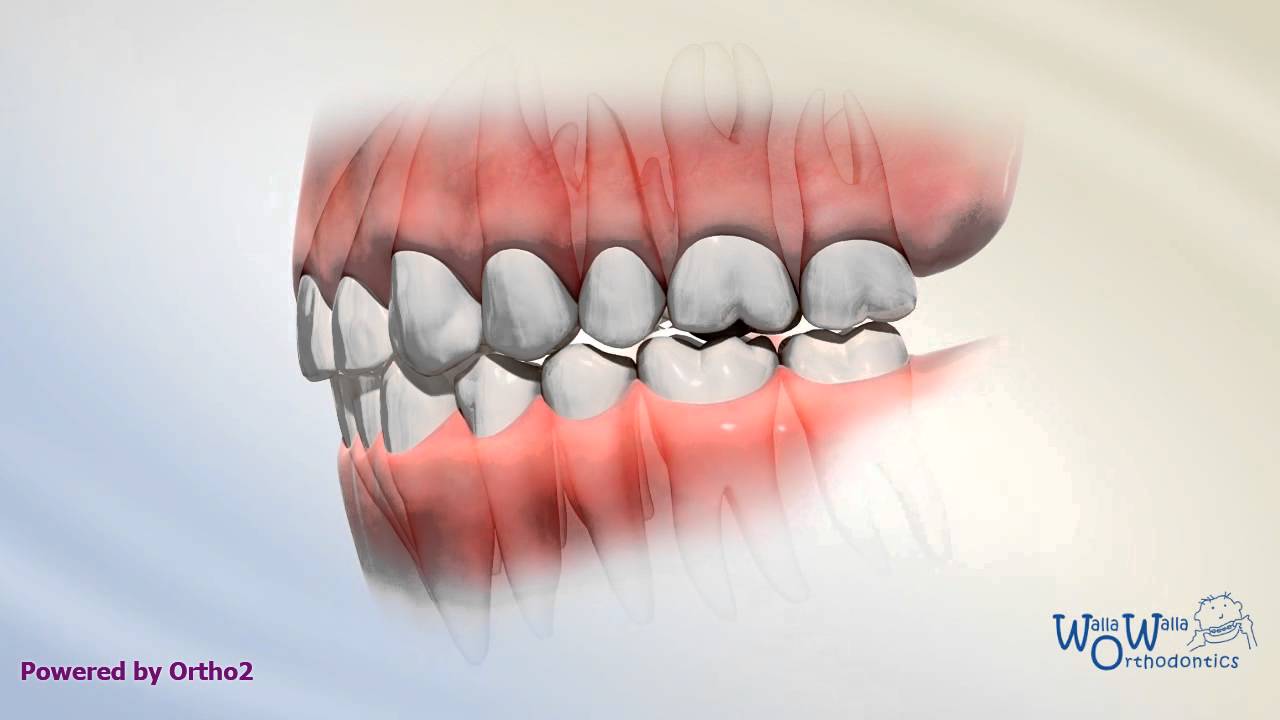

Class I Crowding Youtube An overview of the case resulted in the damon ultima psl with variable torques utilized correcting the malocclusion with resolution of the significant crowding and lack of overbite along with substantial arch development. Despite this strong molar connection, patients with class i malocclusion may show additional dental anomalies, such as crowding, spacing, rotations, or misalignment of individual teeth . understanding how and when this malocclusion develops is important to comprehend its etiology. Crowding is an increasingly common type of malocclusion caused by a discrepancy in tooth jaw size that leads to twisted and misaligned teeth. two methods to treat this malalignment are tooth material reduction and arch width expansion. Class i malocclusions with severe crowding and tooth size discrepancies may be successfully treated orthodontically with extraction therapy, and co management with other specialists. correction of the discrepancies will optimize occlusal result (overjet, overbite, midline shift, and smile esthetics). Ackerman profitt system of classification involves steps to assess malocclusion. crowding, spacing, cross bite, open bite, deep bite, bimaxillary protrusion, rotations, and other dental problems are discussed, along with their causes and management options. Despite all this, treatment results do not always remain stable. the most common type of malocclusion in mixed dentition patients is crowding. it occurs when there is a discrep ancy between the size of the tooth mass and the size of the supporting bony bases. two treatment strategies used to correct this problem are extraction and expan sion.

Crowding Youtube Crowding is an increasingly common type of malocclusion caused by a discrepancy in tooth jaw size that leads to twisted and misaligned teeth. two methods to treat this malalignment are tooth material reduction and arch width expansion. Class i malocclusions with severe crowding and tooth size discrepancies may be successfully treated orthodontically with extraction therapy, and co management with other specialists. correction of the discrepancies will optimize occlusal result (overjet, overbite, midline shift, and smile esthetics). Ackerman profitt system of classification involves steps to assess malocclusion. crowding, spacing, cross bite, open bite, deep bite, bimaxillary protrusion, rotations, and other dental problems are discussed, along with their causes and management options. Despite all this, treatment results do not always remain stable. the most common type of malocclusion in mixed dentition patients is crowding. it occurs when there is a discrep ancy between the size of the tooth mass and the size of the supporting bony bases. two treatment strategies used to correct this problem are extraction and expan sion.

Class I Malocclusion Youtube Ackerman profitt system of classification involves steps to assess malocclusion. crowding, spacing, cross bite, open bite, deep bite, bimaxillary protrusion, rotations, and other dental problems are discussed, along with their causes and management options. Despite all this, treatment results do not always remain stable. the most common type of malocclusion in mixed dentition patients is crowding. it occurs when there is a discrep ancy between the size of the tooth mass and the size of the supporting bony bases. two treatment strategies used to correct this problem are extraction and expan sion.